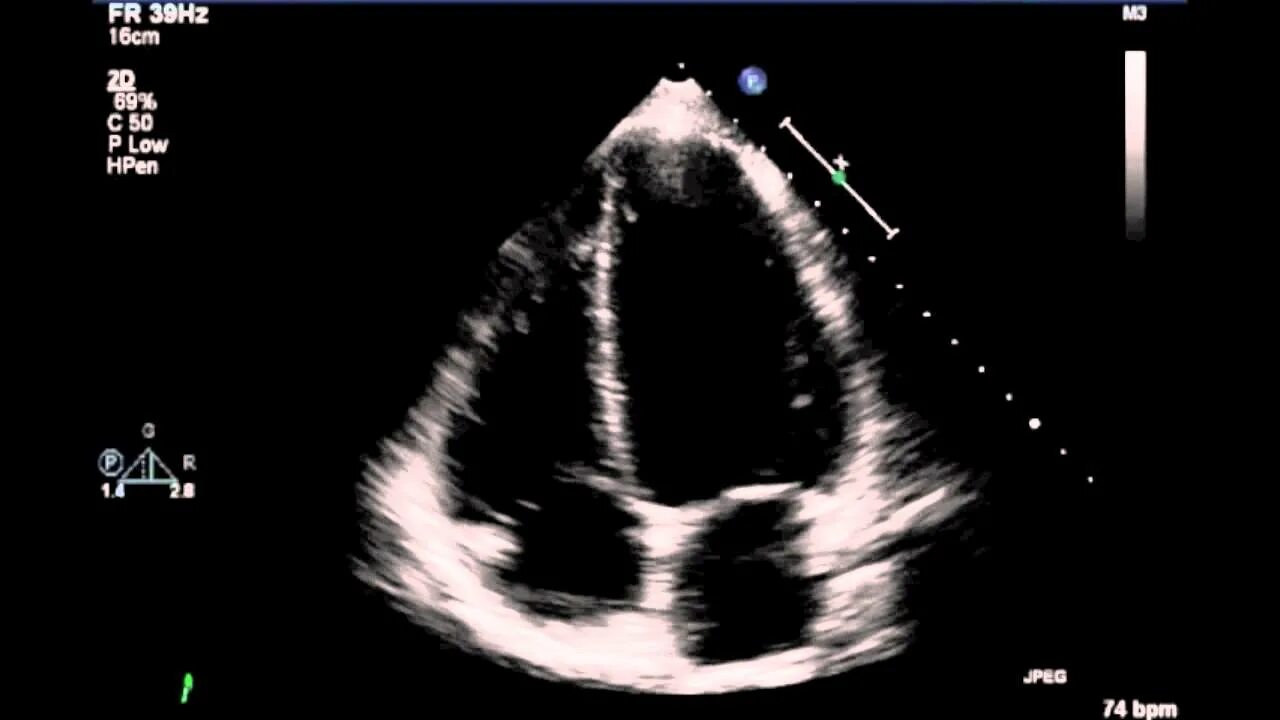

Эх сердца